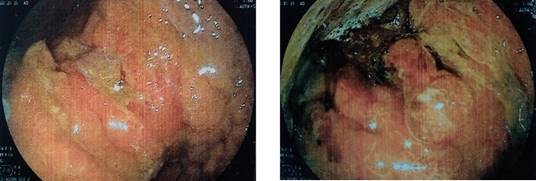

Se trata de un paciente masculino de 68 años, con antecedente de diabetes mellitus tipo 2, tabaquismo y etilismo crónico por más de 20 años. Niega antecedentes quirúrgicos. Inicia padecimiento al presentar cuadros intermitentes de distensión abdominal, dispepsia, disfagia progresiva de sólidos a líquidos. Niega pérdida de peso o datos de sangrado de tubo digestivo. Se inicia protocolo de estudio con tomografía axial computarizada con contraste intravenoso reportando tumor renal derecho de 7 x 6 x 4 cm de bordes redondeados, definidos, heterogénea, centro hipodenso en relación con degeneración quística o necrótica (Figura 1); presentando signo de la garra tras la administración de contraste intravenoso, con realce en 20 UH, con fase trifásica retardada, realce de la lesión con 10 UH; se observa estómago distendido, engrosamiento de la mucosa antral y pilórica de 1.7 cm, no se observan metástasis hepáticas ni a distancia en la tomografía. Se realiza panendoscopia que muestra neoplasia gástrica infiltrante (adenocarcinoma Borrmann II) (Figura 2). El resultado histopatológico de la biopsia gástrica reporta: adenocarcinoma poco diferenciado infiltrante difuso de células en anillo de sello. El marcador CA 19-9 con valores de 126 U/ml con estatificación clínica del cáncer gástrico. Se lleva a cabo la intervención quirúrgica con gastrectomía total, linfadenectomía D1, esofagoyeyuno-anastomosis con engrapadora circular de 29 mm y enteroentero-anastomosis-latero-terminal con engrapadora lineal 55 mm en Y-de-Roux (Figuras 3 y 4 ). Durante el mismo procedimiento quirúrgico se realiza nefrectomía radical derecha con los siguientes hallazgos: líquido libre cetrino escaso, riñón derecho con tumor sólido en polo superior de 10 x 5 cm, vena renal sin trombo; estómago con tumor en la curvatura menor, antro y píloro, extensión del tejido tumoral hacia tronco celíaco, incluyendo arteria gástrica izquierda, arteria hepática hasta la gastroduodenal. Tumor en cara posterior de estómago con adherencia a cuerpo de páncreas, implantes tumorales en mesocolon transverso cerca del ángulo de Treitz, adenomegalias en epiplón mayor, unión esofagogástrica sin actividad tumoral. Con estatificación de T4aN2M0 del cáncer gástrico, el cáncer renal con estatificación de T2bN0M0. Paciente cursó con buena evolución postquirúrgica, sin datos de fuga de anastomosis, toleró la vía oral y deambulación al quinto día postquirúrgico y con mejoría clínica, por lo cual se decide su egreso en su séptimo día de estancia.